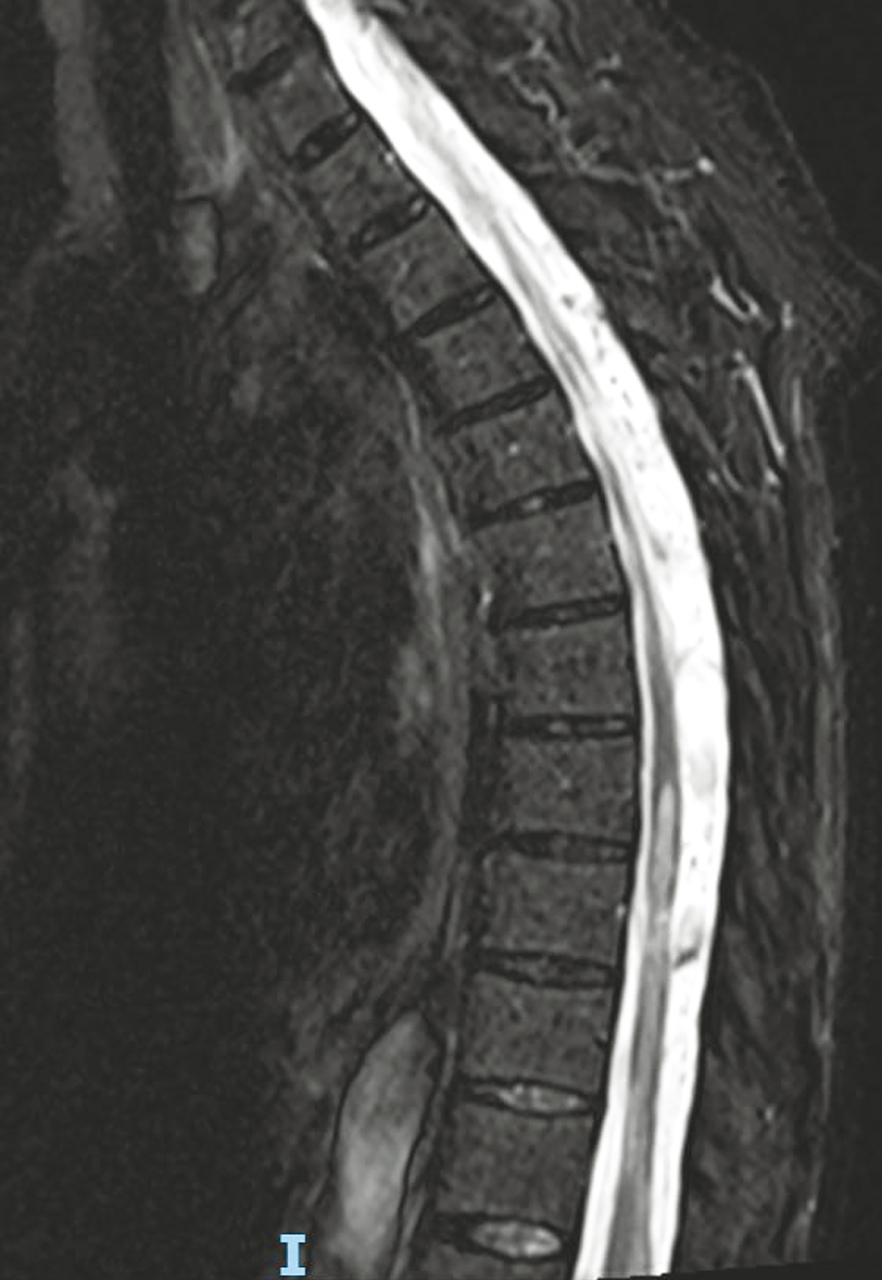

Une femme de 71 ans a une paraplégie d’apparition progressive. Quel est votre diagnostic ? Compression médullaire Syringomyélie Syndrome de Guillain Barré Myélite Spondylodiscite OK Valider mes réponses